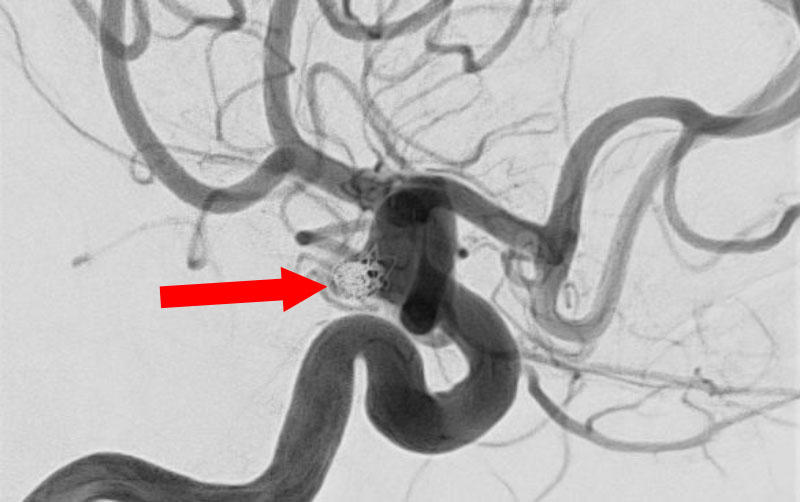

No.1596 手術中